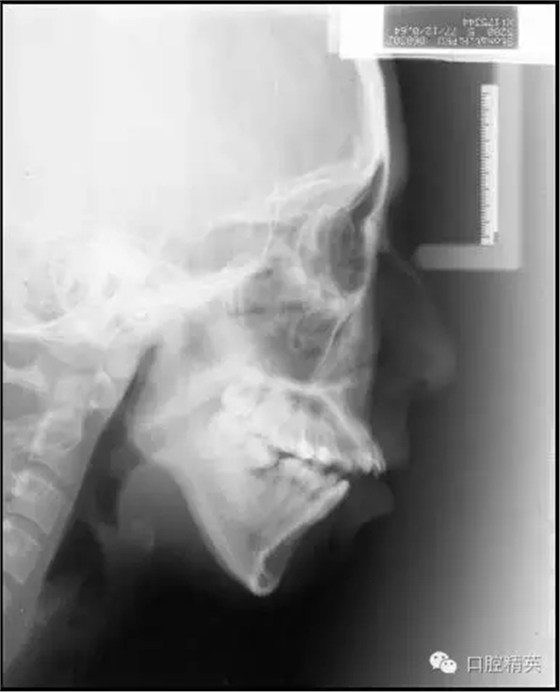

自上個世紀末開始至今,微螺釘種植體支抗在正畸領(lǐng)域的應用已有近20年的歷史。而隨著其被越來越廣泛靈活地應用于正畸臨床工作中,其在垂直向上的獨特優(yōu)勢也越來越突出,大致可以歸納為以下六個方面:高角病例全方位垂直向控制;改善露齦微笑——壓低上前牙;打開重度深覆合——壓低下前牙或同時壓低上前牙;矯正平面傾斜——壓低一側(cè)牙齒;壓低過萌長磨牙——壓低磨牙;直立近中傾斜的磨牙——直立并壓低磨牙。本文將以結(jié)合典型病例的方式對以上六種微螺釘種植體支抗在垂直向上的應用一一論述說明。

后部垂直向控制是基于高角骨面型的形成機制提出的。研究指出,高角骨面型的形成主要是由于相對較小的髁突垂直生長量,和相對較大的上頜骨垂直生長量及上下頜后牙牙槽突垂直生長量,所共同導致的下頜骨后下旋轉(zhuǎn)所致。

簡言之,即髁突與磨牙區(qū)的垂直生長量失衡。對這類患者,即使是正處于生長發(fā)育期者,我們也很難寄希望于其髁突的生長在正畸治療中或治療后能自動超過磨牙區(qū)的垂直生長,進而控制住其下頜平面,因為通?;颊咴瓉淼腟N-MP角越大,下頜平面隨生長發(fā)育會變得越陡。

既然我們很難改變患者髁突生長不足的問題,就只好從控制其上頜骨及磨牙區(qū)的垂直生長著手了,由于抑制生長本非易事,控制患者的磨牙高度就成了控制其下頜平面最切實可行的手段。而通過壓低磨牙來控制高角患者的下頜平面,乃至實現(xiàn)其下頜平面的前上旋轉(zhuǎn)正是后部垂直向控制的概念及意義所在(圖1)。

前部垂直向控制則是指控制上前牙向上向后移動。 這一概念源于Tweed-Merrifield技術(shù)的方向性力系統(tǒng)。這一技術(shù)一直被認為能夠為Ⅱ類高角患者帶來最佳的矯治效果,技術(shù)標志之一就是著名的方向性力系統(tǒng),即通過控制患者的下后牙和上前牙來控制其下頜平面和合平面,實現(xiàn)這一控制的所有力的合力矢量均需向上向前,所需方向性力由牽引皮圈和可調(diào)整方向的J鉤頭帽提供。最終實現(xiàn)下切牙直立于基骨之上,上前牙向上向后移動,為下頜骨的前上旋轉(zhuǎn)創(chuàng)造條件,而這也正是前部垂直向控制的概念及意義所在(圖2)。